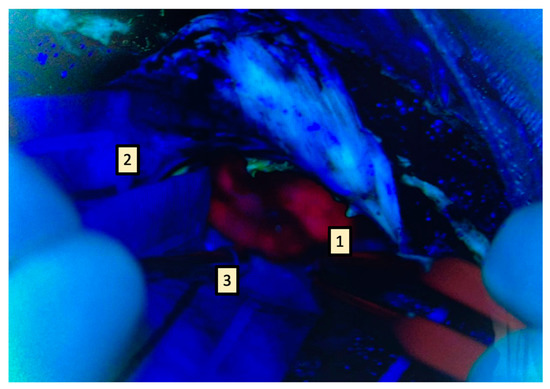

Figure 5.

Research suggests that 5-ALA has mainly a refinement role after gross resection. The lava red area represents the tumor core (1) and the pale area represents the infiltrative margins (2), surrounded by the negative fluorescent area (3). Where feasible, it is paramount to extend resection, including the peritumoral “pale” area, without pushing it over neurophysiological boundaries.